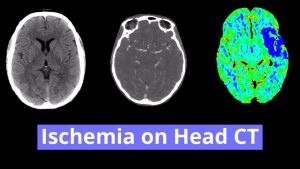

Findings

- Area of loss of gray-white differentiation in the left parietal lobe along the MCA/PCA watershed zone

- Hypodensity in the left caudate head

- Scattered subcortical and periventricular white matter hypodensities

- Intracranial atherosclerosis

Diagnosis

- Acute left MCA/PCA and ACA/MCA watershed infarcts

- Acute left caudate head infarct

Area of loss of gray-white differentiation in the left parietal lobe along the MCA/PCA watershed zone concerning for acute ischemia. No evidence of hemorrhagic transformation or associated mass effect. Recommend brain MRI without contrast for further evaluation.

Age-indeterminate left caudate head infarct, which can also be further evaluated with MRI.

No acute hemorrhage or mass effect.